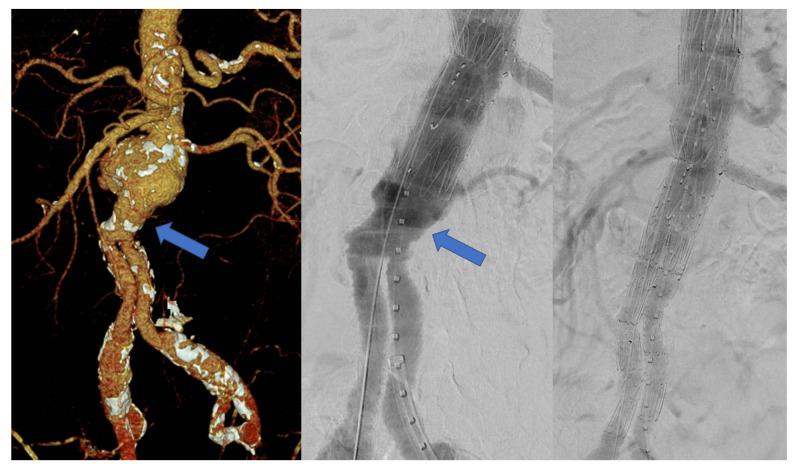

This study aims to assess the mid-term results of fenestrated endovascular aneurysm repair (FEVAR) for the treatment of proximal aortic pathology after previous open surgical repair (OSR). All patients with a previous history of OSR of an abdominal aortic aneurysm undergoing a FEVAR procedure between October 2010 and November 2021 were included. The endpoints of the study were technical success, mortality, target vessel patency and reinterventions during follow-up. Thirty-five patients (34 male, mean age 72.9 ± 7 years) were included. The median interval from the primary surgery to the FEVAR procedure was 136 months (range 47-261). The indication for treatment was a para-anastomotic aneurysm in 18 (51%) patients and a true aneurysm due to progression of disease in 17 (49%) patients. Technical success was achieved in 33 (94%) patients. There was one (3%) early death due to postoperative bleeding from a renal artery. Estimated survival at 12, 24 and 36 months was 89.1% ± 6%, 84.4% ± 7.3% and 84.4% ± 7.3%, respectively. There was no aneurysm-related mortality. One (3%) target vessel occluded during follow-up and three (9%) patients underwent late reinterventions. In conclusion, FEVAR is a safe and effective alternative for the endovascular treatment of para-anastomotic aneurysms/pseudoaneurysms after OSR showing high technical success, low mortality and morbidity, and good mid-term outcomes.

本研究旨在评估开窗式血管腔内动脉瘤修复术(FEVAR)治疗既往开放性手术修复(OSR)后近端主动脉病变的中期结果。纳入2010年10月至2021年11月期间接受FEVAR手术且既往有腹主动脉瘤OSR病史的所有患者。研究终点为技术成功率、死亡率、靶血管通畅率及随访期间的再次干预情况。共纳入35例患者(34例男性,平均年龄72.9±7岁)。从初次手术到FEVAR手术的中位间隔时间为136个月(范围47 - 261个月)。治疗指征为18例(51%)患者的吻合口旁动脉瘤和17例(49%)患者因疾病进展导致的真性动脉瘤。33例(94%)患者获得技术成功。有1例(3%)患者因肾动脉术后出血早期死亡。12个月、24个月和36个月的预计生存率分别为89.1%±6%、84.4%±7.3%和84.4%±7.3%。无动脉瘤相关死亡。随访期间1例(3%)靶血管闭塞,3例(9%)患者接受了晚期再次干预。总之,FEVAR是OSR后吻合口旁动脉瘤/假性动脉瘤血管腔内治疗的一种安全有效的替代方法,技术成功率高,死亡率和发病率低,中期结果良好。